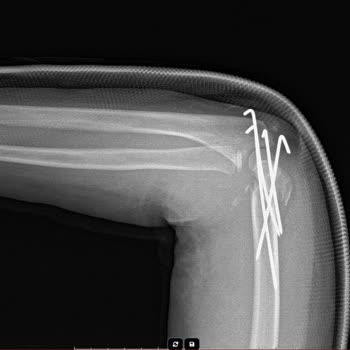

Zeytinburnu'daki Koç Üniversitesi acil bölümüne 03.10.2024 tarihinde kızım z. D**. Ş. Sol ayak bileğinde bileğinde şiddetli ağrıyla acil bölümüne götürdüm. Acilde röntgen çekildi. Sol ayağında olmasına rağmen 2 ayağını da röntgen çekilmiş olduğunu gördük. Acil de ayağında kırık olmadığı ortopedi dok...